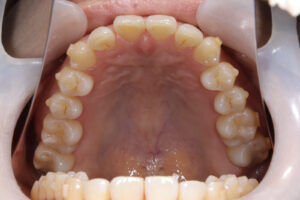

Invisalign correction failure

orthodontic treatment

表側矯正での再治療

治療方針

インビザラインと歯周病の相性はよくありません。

それは、インビザラインの着脱で歯が揺り動かされる事とアタッチメントの下は磨けないからです。

そのため、歯周病を悪化させる方向になってしまいます。

歯周病治療の場合、表側のワイヤー矯正をお勧めします。

それは、まだ歯磨きがやりやすい矯正になるからです。